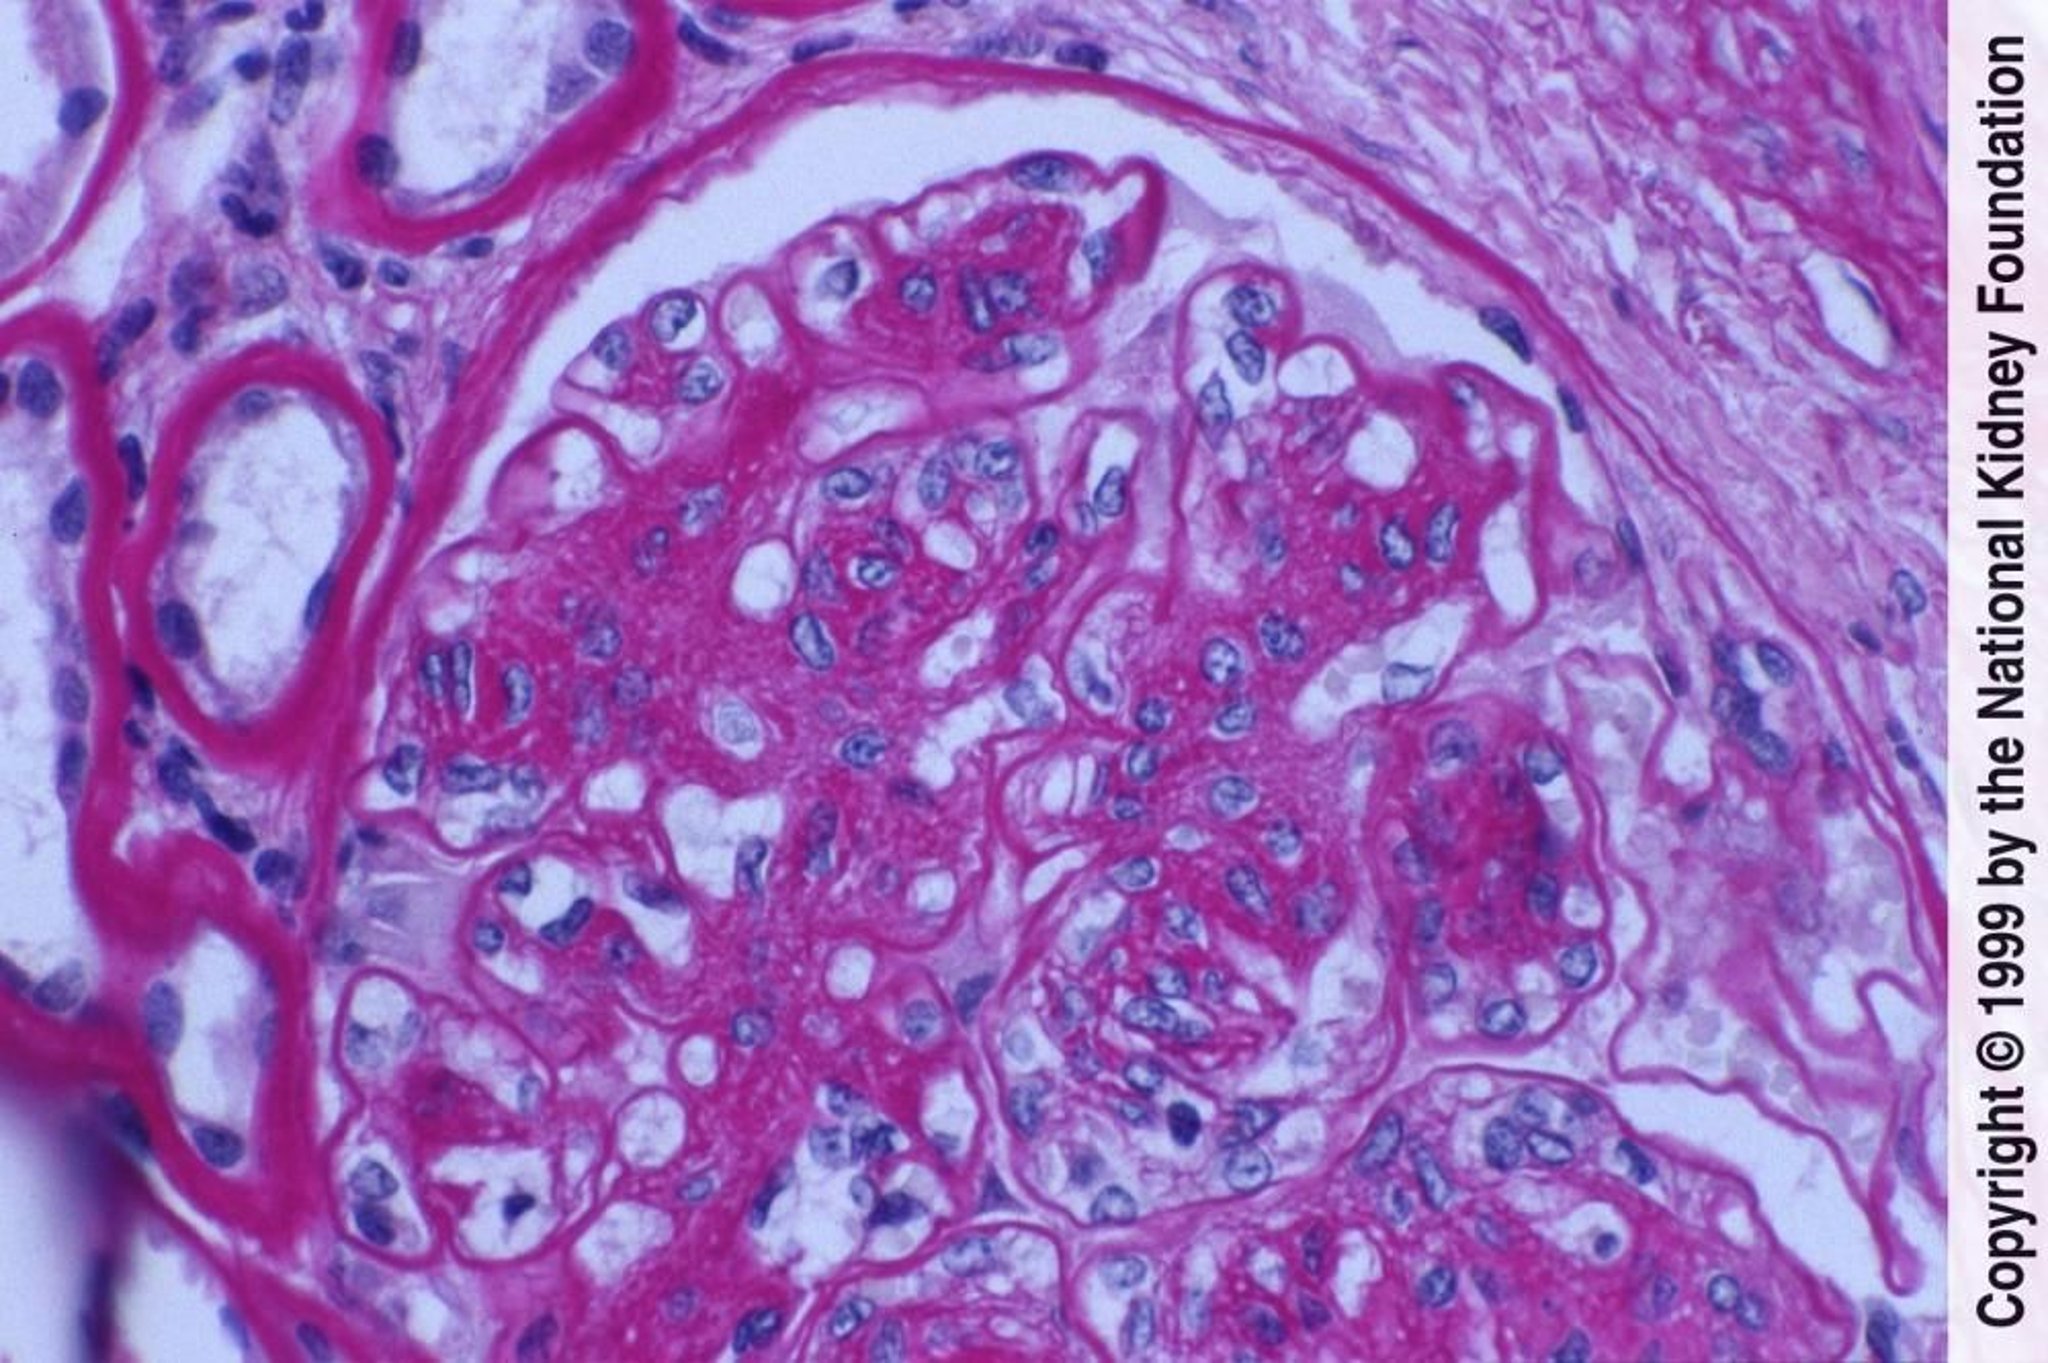

Nefropatía diabética (proliferación de células mesangiales y expansión de la matriz)

La proliferación de células mesangiales y la expansión de la matriz con daño endotelial se manifiestan aquí como engrosamiento de las membranas basales glomerulares sin depósitos evidentes de inmunocomplejos (tinción de ácido peryódico de Schiff, ×400).

Image provided by Agnes Fogo, MD, and the American Journal of Kidney Diseases' Atlas of Renal Pathology (véase www.ajkd.org).